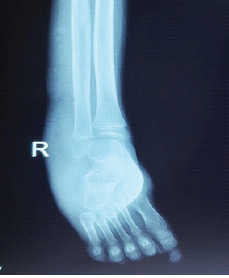

A Case Series of Functional and Radiological Outcome of Comminuted Distal Radius Fractures Treated with Bridging External Fixator with Optional Percutaneous K-wires

Subramanya Gandhi , Mohamed Safiullah , Vijay Narasimman Reddy , Ashin khan , Mervin Rosario P M